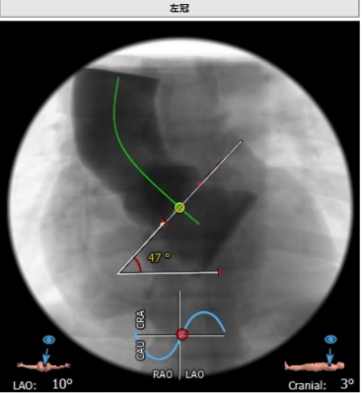

心脏角度:47°,升主动脉40mm:35.3mm

释放体位:LAO:1°,CRA:7°左冠线切位:LAO:10°,CRA:3°